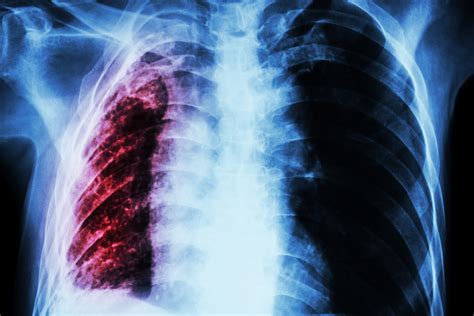

Atelectasis is a condition where the lung tissue collapses or fails to expand properly, leading to reduced oxygen intake. When this condition is associated with lung cancer, it is referred to as Atelectasis Lung Cancer. This type of cancer can be particularly challenging to diagnose and treat due to the underlying lung collapse, which can obscure symptoms and complicate diagnostic procedures.

Diagnosing Atelectasis Lung Cancer involves a combination of medical history, physical examination, and diagnostic tests. The diagnostic process typically includes:

• Chest X-ray: An initial imaging test to detect any abnormalities in the lungs.